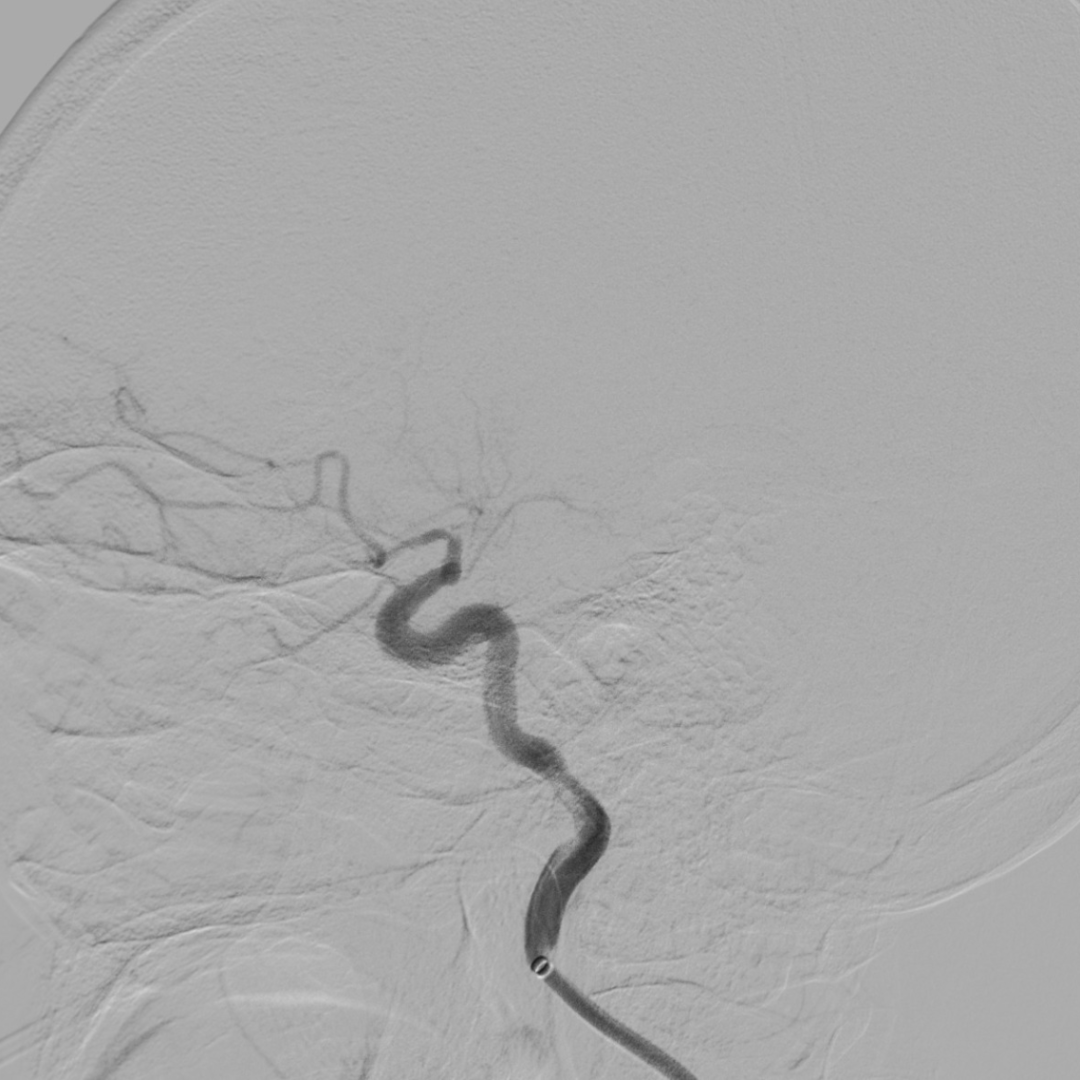

建立通路:

泥鳅塑型,携带125cm长SIM2进入右颈总。

5.5F IntroSky X导管鞘顺利绕过迂曲段进入颈总动脉。

通路尽量高到位,同时注意避免血管痉挛、血流阻断。